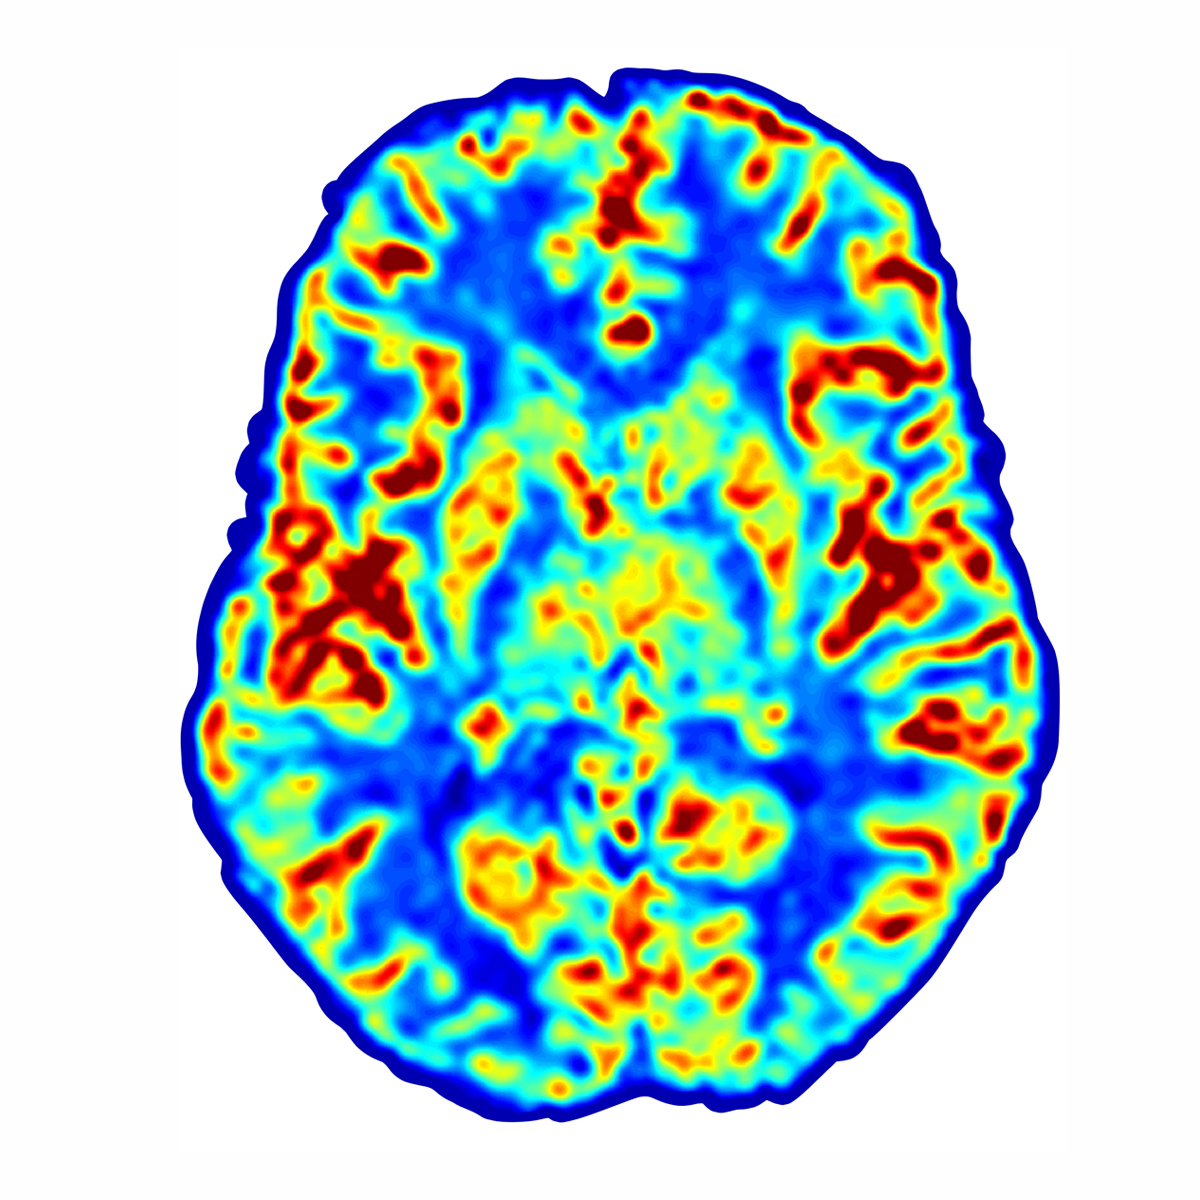

SPECT Scan of Human Brain

Brain

Rejuvenation of injured brain tissue, restoring some or all functions in

the damaged tissue, including memory, attention, focus, information processing and more.

At Aviv, we first determine the severity of the brain injury based on the results of an MRI, physical, cognitive, and neurological tests to assess the damage and determine suitability for treatment.  The assessment is conducted by Aviv certified medical staff including physicians, neuropsychologists, physiotherapists, physiologists, and nurses. This involves the most advanced brain imaging tests suited to your needs, such as functional MRI and SPECT scans.